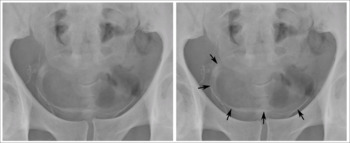

Calcification of the bladder wall on a plain X-ray image of the pelvis, in a 44-year-old sub-Saharan man, due to urinary schistosomiasis

The worms of S. haematobium migrate to the veins around the bladder and ureters.[22] This can lead to blood in the urine 10 to 12 weeks after infection.[14][18] Over time, fibrosis can lead to obstruction of the urinary tract, hydronephrosis, and kidney failure.[14][18] Bladder cancer diagnosis and mortality are generally elevated in affected areas; efforts to control schistosomiasis in Egypt have led to decreases in the bladder cancer rate.[18][24] The risk of bladder cancer appears to be especially high in male smokers, perhaps due to chronic irritation of the bladder lining allowing it to be exposed to carcinogens from smoking.[20][22]